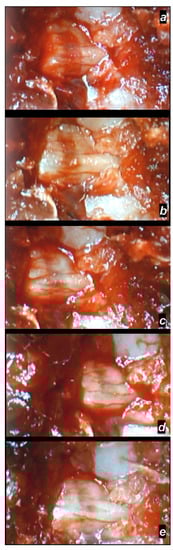

Delayed Post-Injury Course, Immediate Effect

3.2.3. Delayed Post-Injury Course, Long-Term Effect